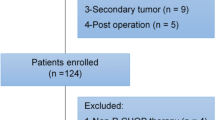

One hundred and eighteen patients with newly diagnosed DLBCL treated with R-CHOP/R-CHOP-like therapy and undergoing diagnostic work-up including baseline 18F-FDG PET/CT in the period 2007–2012 at Aalborg University Hospital were included in this retrospective study. Clinical information including outcome parameters was collected from medical records. The Danish Data Protection agency (ref 1-16-02-88-15) and the Danish Ministry of Health approved the study (ref 3-3013-860/1/).

A total of 118 patients (76 males and 42 females) with median age 66 (range 18–88) were included (Table 2). According to the international prognostic index (IPI), 60 patients (50.8%) were low/low-intermediate risk, 29 (24.6%) were high-intermediate, and 23 (19.5%) were high-risk. Information on IPI was not available in 5 patients. Median follow-up was 67 months (reverse Kaplan-Meier method) and the overall 5-year PFS and overall survival (OS) estimates were 65.7% and 68.9%, respectively (Fig. 2 for IPI-specific survival curves). Treatment regimens were R-CHOP (n = 104, 88.1%), R-CHOEP (n = 12, 10.2%), and R-CEOP (n = 2, 1.7%). Two patients turned out to be CD20 negative and thus had rituximab removed from their treatment regimens.